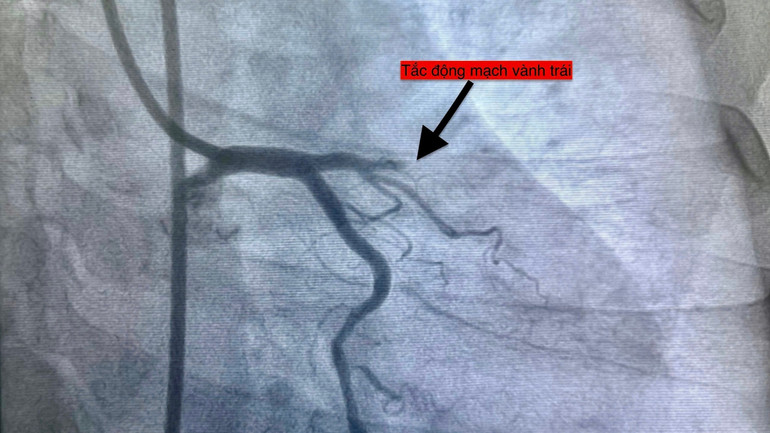

Hình ảnh chụp các ca bệnh nhồi máu cơ tim.